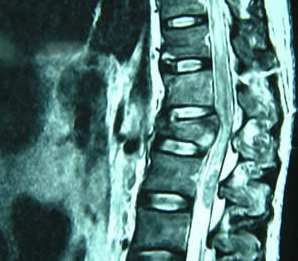

脊柱骨折和脊髓损伤

脊髓损伤CT和MRI检查的作用_健康_南阳新闻